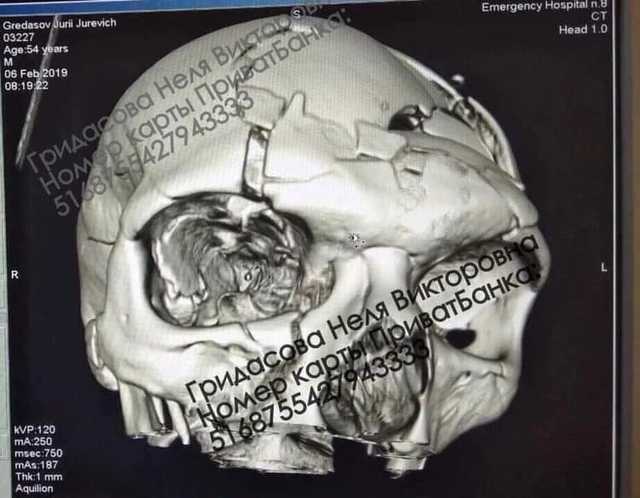

Он рассказал, что Гридасов выходил из машины, когда на него напали неизвестные и дважды ударили по голове тяжелым предметом — трубой или битой. В результате у пострадавшего разрушен череп. Ему сделали операцию в днепровской больнице имени Мечникова, удалив обломки костей, очаги кровоизлияний и контузии. Также ему сделали пластику свода черепа титановой пластиной.